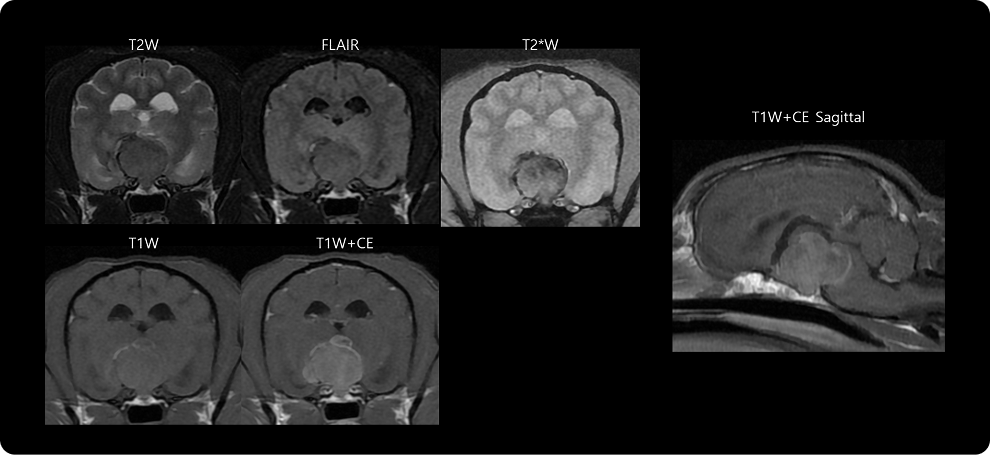

· 뇌 MRI 검사

신경계 증상이 동반된 경우, 시상하부의 종양성 변화 여부를 확인합니다.